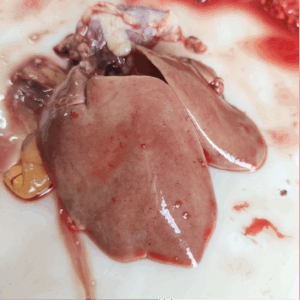

- Liver palpated and checked for any lesion on the surface and by cutting at several points.

Figure 7. Pale liver with petechial haemorrhage